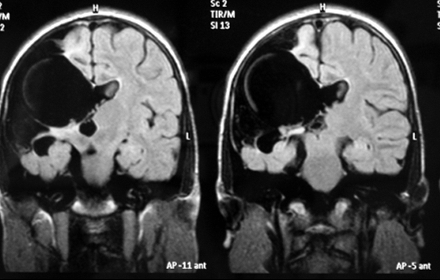

On cranial MRI, images of right-sided unilateral parietal clefts were detected lined by gray matter. The clefts were typical of open-lip schizencephaly, showing communication of the lateral ventricles and subarachnoid space (Fig 1).

Figure 1: T2-weighted FLAIR MRI scan of the patient. Right-sided unilateral parietal clefts were detected, lined by gray matter, connected with right lateral ventricle, septum pellucidum hypoplasia.

The septum pellucidum was partially underdeveloped. The optic nerves and chiasm were normal and the interhemispheric fissure was intact. Compensatory enlargement of the right lateral ventricle was also detected, without a midline shift.